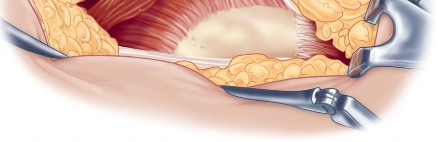

Once the anterior capsular exposure is achieved, a T-shaped or H-shaped capsulotomy is performed. The hip is then dislocated anteriorly with external rotation, extension, and adduction. After the femoral neck osteotomy is completed and the femoral head is removed, attention turns to acetabular preparation.

Acetabular exposure is the most technically demanding aspect of the lateral approach. To optimize exposure, the strategic placement of retractors is paramount. A sharp curved Hohmann retractor is carefully placed over the anterior lip of the acetabulum. The sharp tip must engage the bone securely to prevent slippage. This retractor serves a dual purpose: it retracts the anterior capsule and the elevated abductor-vastus flap anteriorly, providing unimpeded visualization of the anterior and superior acetabular rim.

Additional retractors are utilized to complete the exposure. A blunt Hohmann or Cobra retractor is placed inferiorly beneath the transverse acetabular ligament to retract the inferior capsule and soft tissues. A third retractor may be placed posteriorly. The precise placement of the anterior sharp curved Hohmann is the key to preventing the abductor mass from obscuring the surgeon's view during reaming and cup impaction.